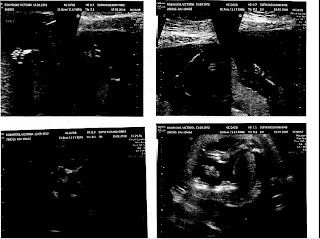

Top Left is 2 feet, top right is upper limbs, bottom left is head profile - that little white bit almost in the centre of the screen is the nasal bone & bottom right is an upside down baby with a leg & foot at the top and an arm & hand in the middle - beats me!

These are from my 4th scan on the 15th of January - we spent ages while the technician checked all the anatomy markers - then had to go out & wait for the baby to change position so she could get a good reading on the heart. All is well. It is so cool to get to see our baby this way, Even if half the time we have no clue as to what we are looking at!